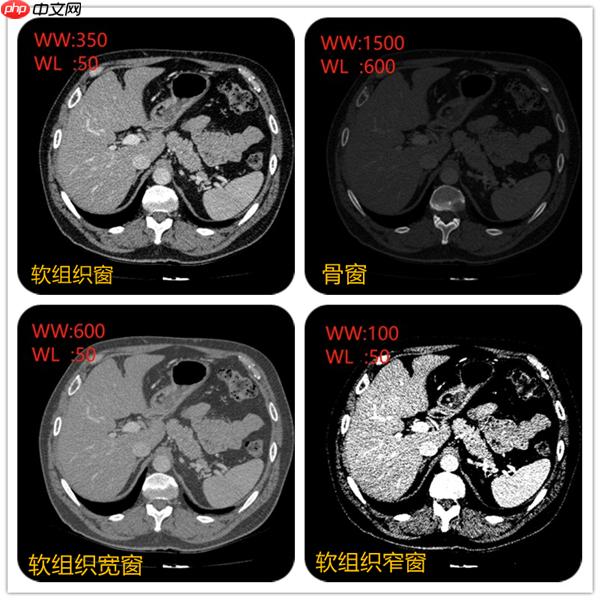

在上面视频可以看到不同窗宽窗位,图像显示不一样。例如当窗宽350,窗位50左右的时候,肝脏、脾脏等软组织密度和对比度都比较合适。当窗宽1600,窗位600左右的时候,肋骨、椎体等骨质的组织的密度和对比度看起来比较合适。不同的组织的CT值可以当成一个固有属性。例如肝脏在50~ 70Hu,脾脏50~ 65Hu等。

例如窗位选择50, 窗宽选择350,图像中可以显示的CT值范围就是(窗位-窗宽/2)至(窗位+窗宽/2)即-140~225,图像显示的时候只要CT值低于-140的组织都会显示黑色。CT值高于255都会显示白色。所以肝的CT值约50,要肝脏对比度显示的好,就先把窗位定在50,在选择窗宽。窗宽约大显示组织密度差别较大的结构,窗宽越窄,组织对比度强,显示密度差别较小的结构。

所以不同的窗宽窗位非常影响诊断医生的判断。例如右上角采用骨窗后对骨质是否有病变有一个很好的诊断。